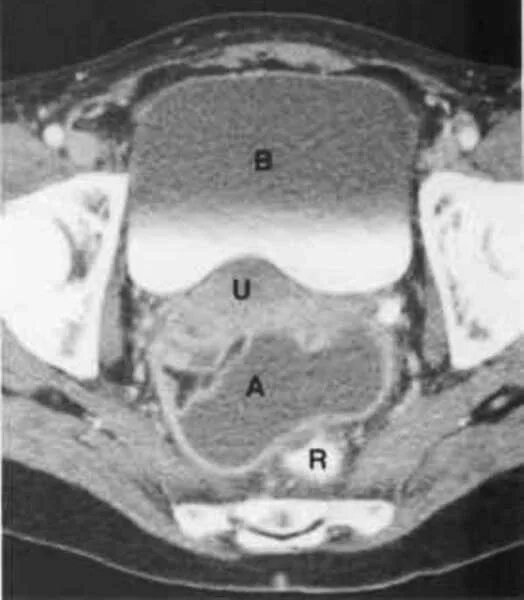

Позадиматочное пространство